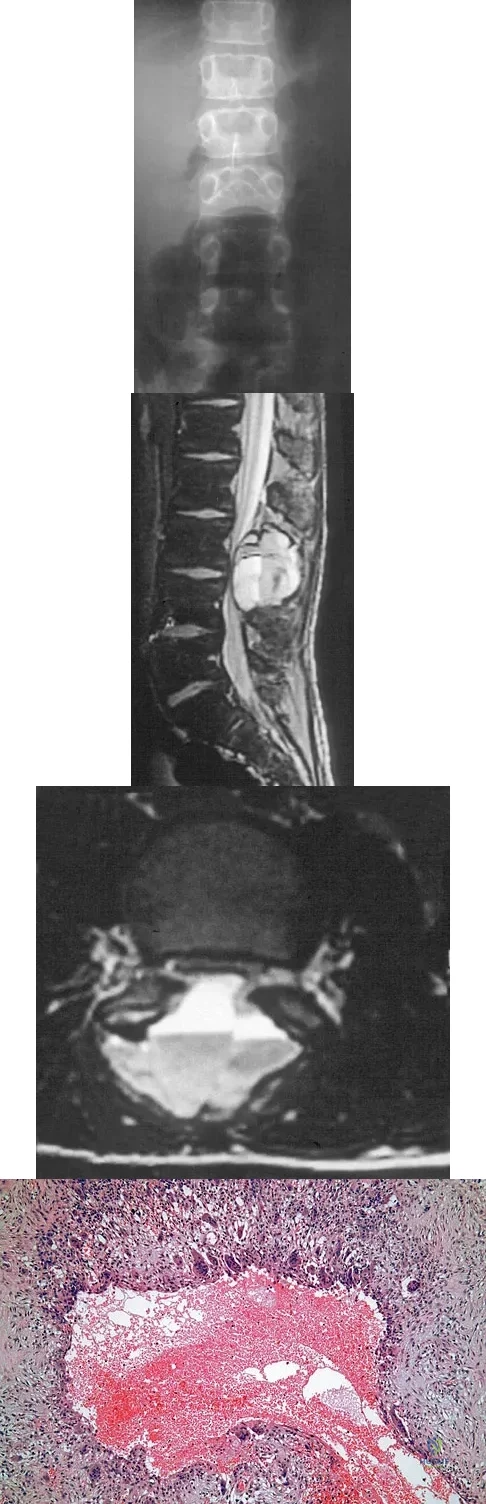

An 8-year-old boy is diagnosed with acute onset cauda equina syndrome. A radiograph, MRI scans, and a biopsy specimen are shown in Figures 57a through 57d. What is the most appropriate treatment?

Explanation